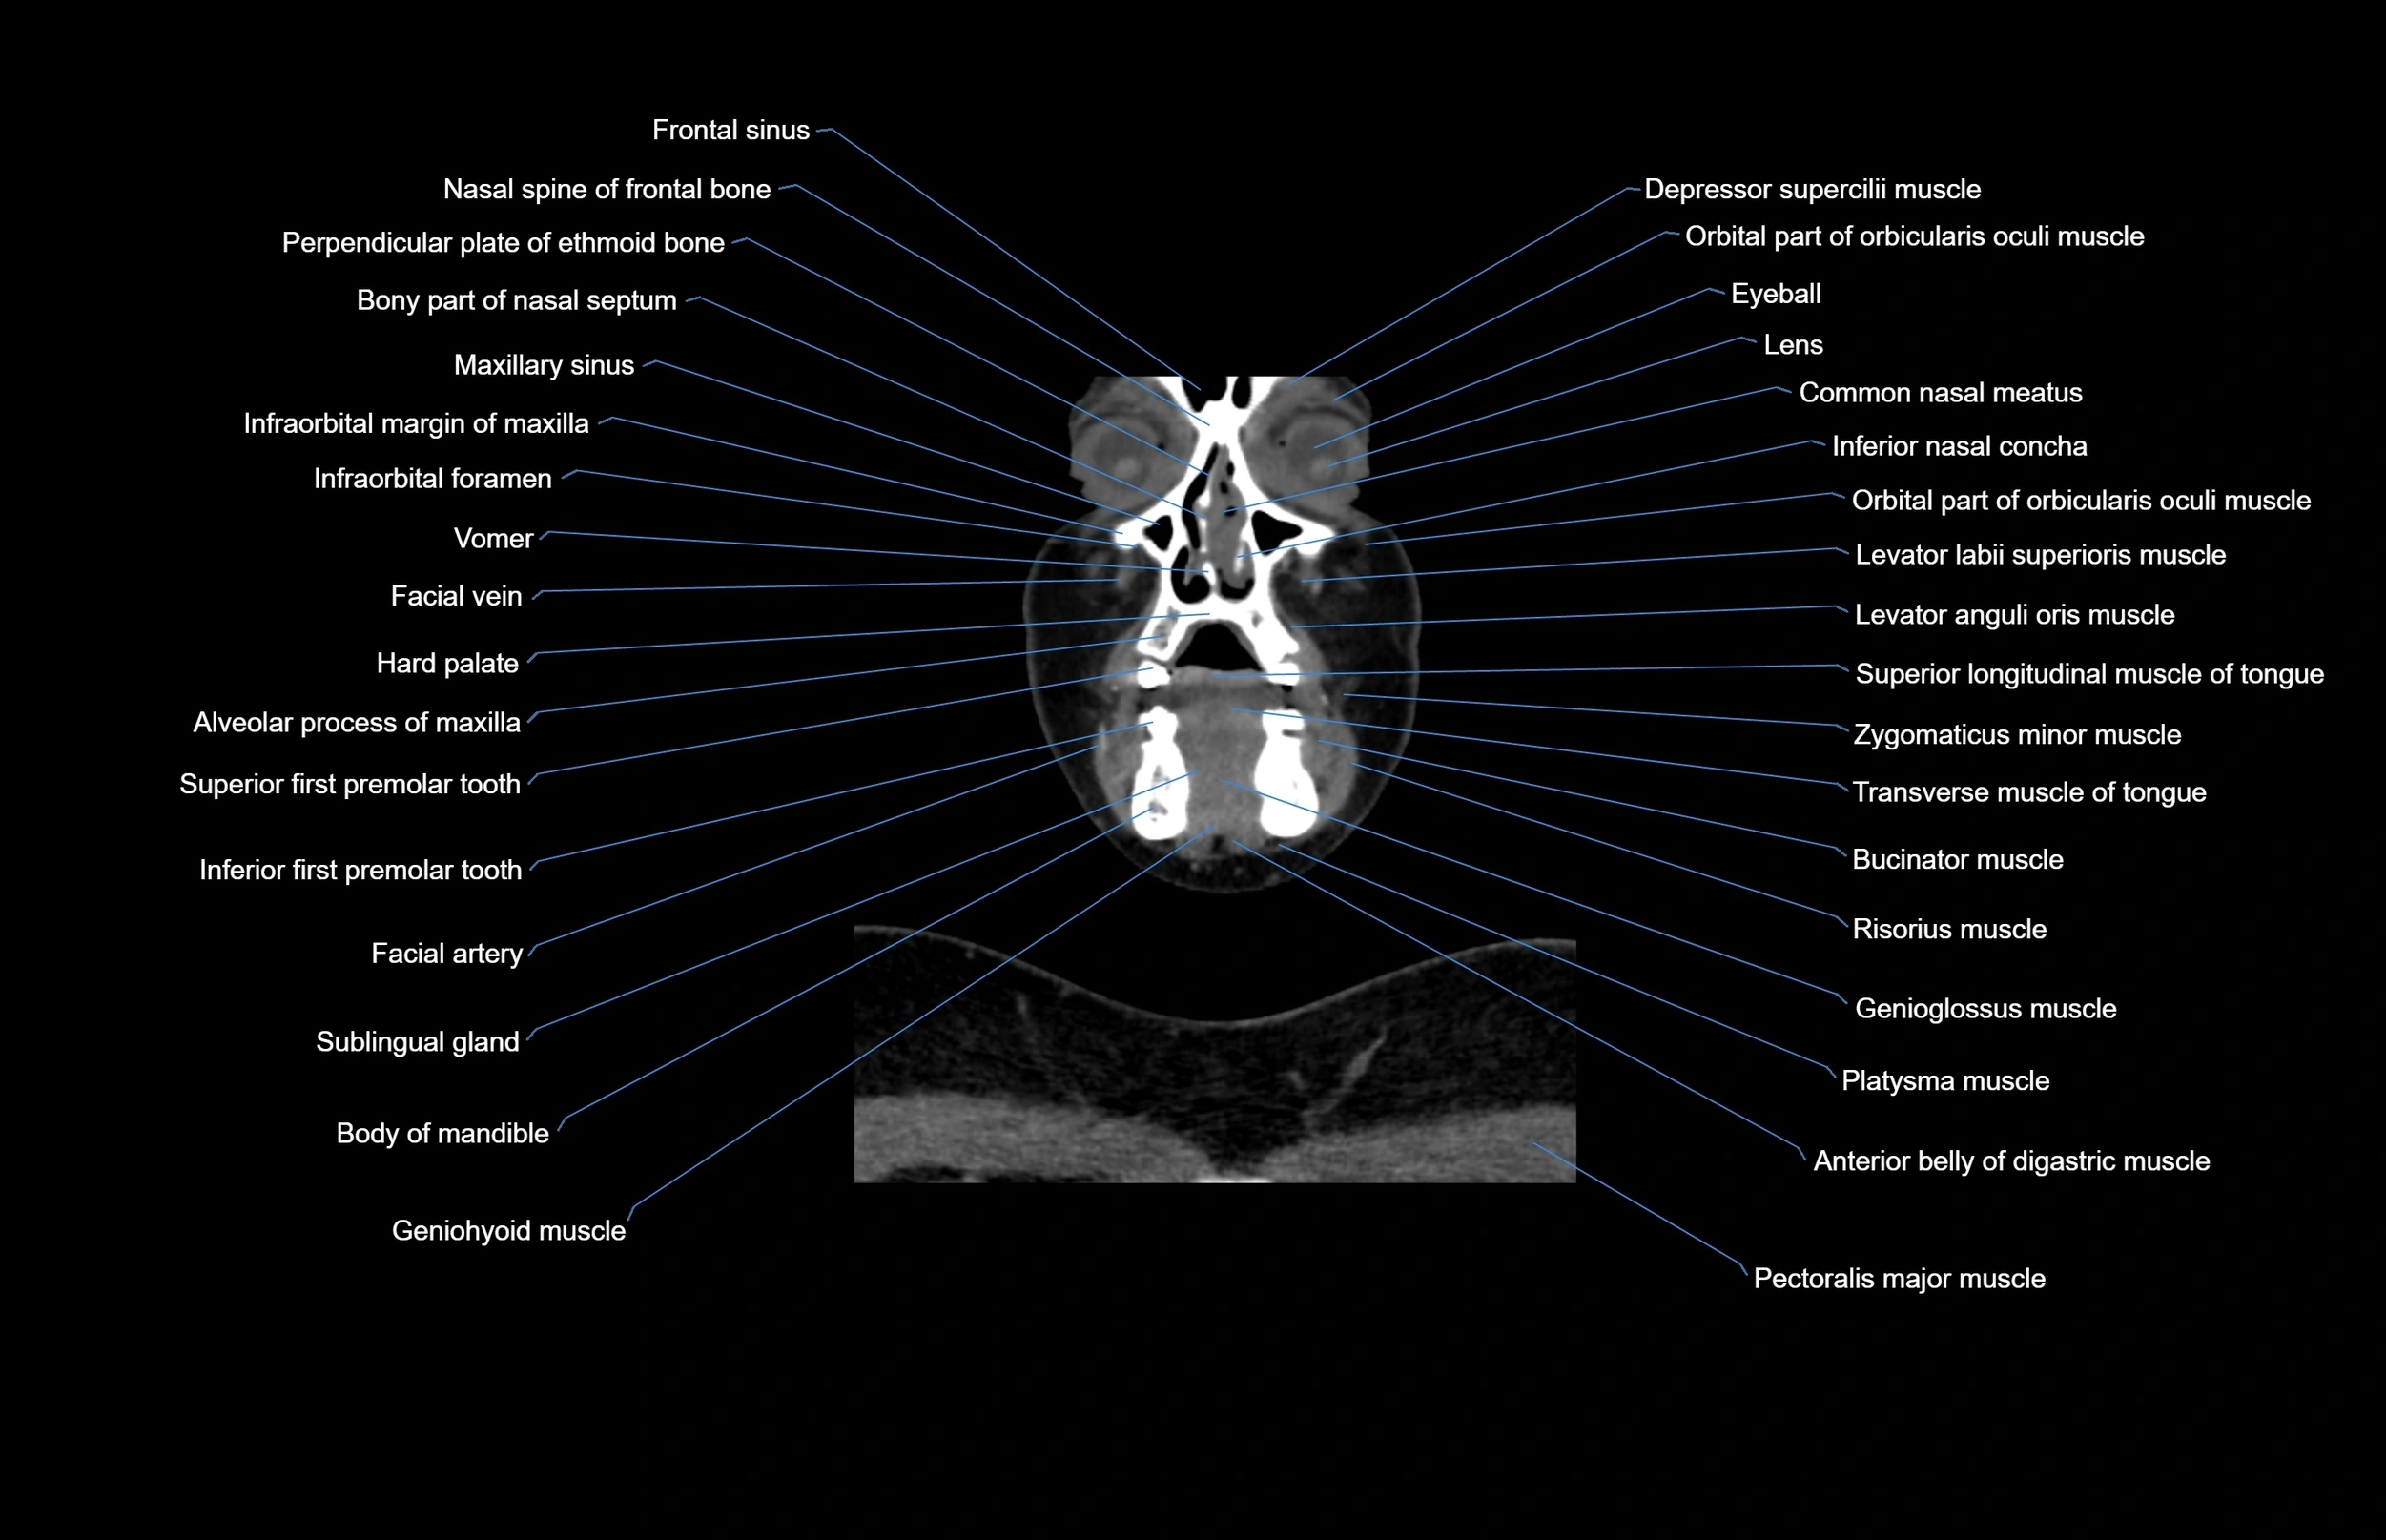

- Alveolar process of maxilla

- Anterior belly of digastric muscle

- Body of mandible

- Buccinator muscle

- Common nasal meatus

- Facial artery

- Facial vein

- Frontal sinus

- Genioglossus muscle

- Hard palate

- Inferior first premolar tooth

- Inferior nasal concha

- Pectoralis major muscle

- Platysma muscle

- Sublingual gland

- Vomer